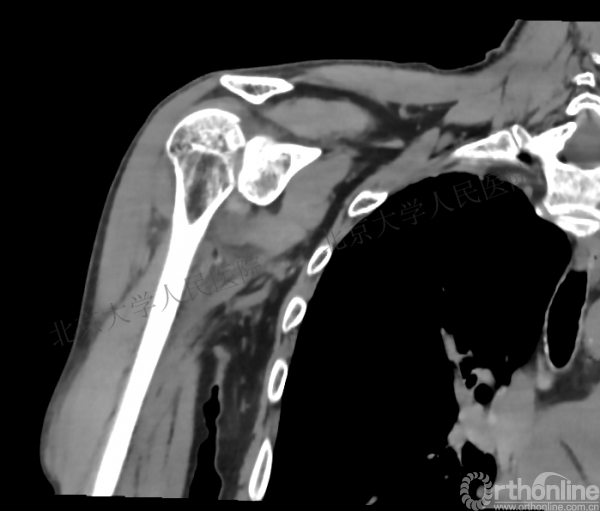

2.CT*—评估缺损大小及关节盂情况

CT检查

1.右肱骨近端骨折

2.右肩关节后脱位